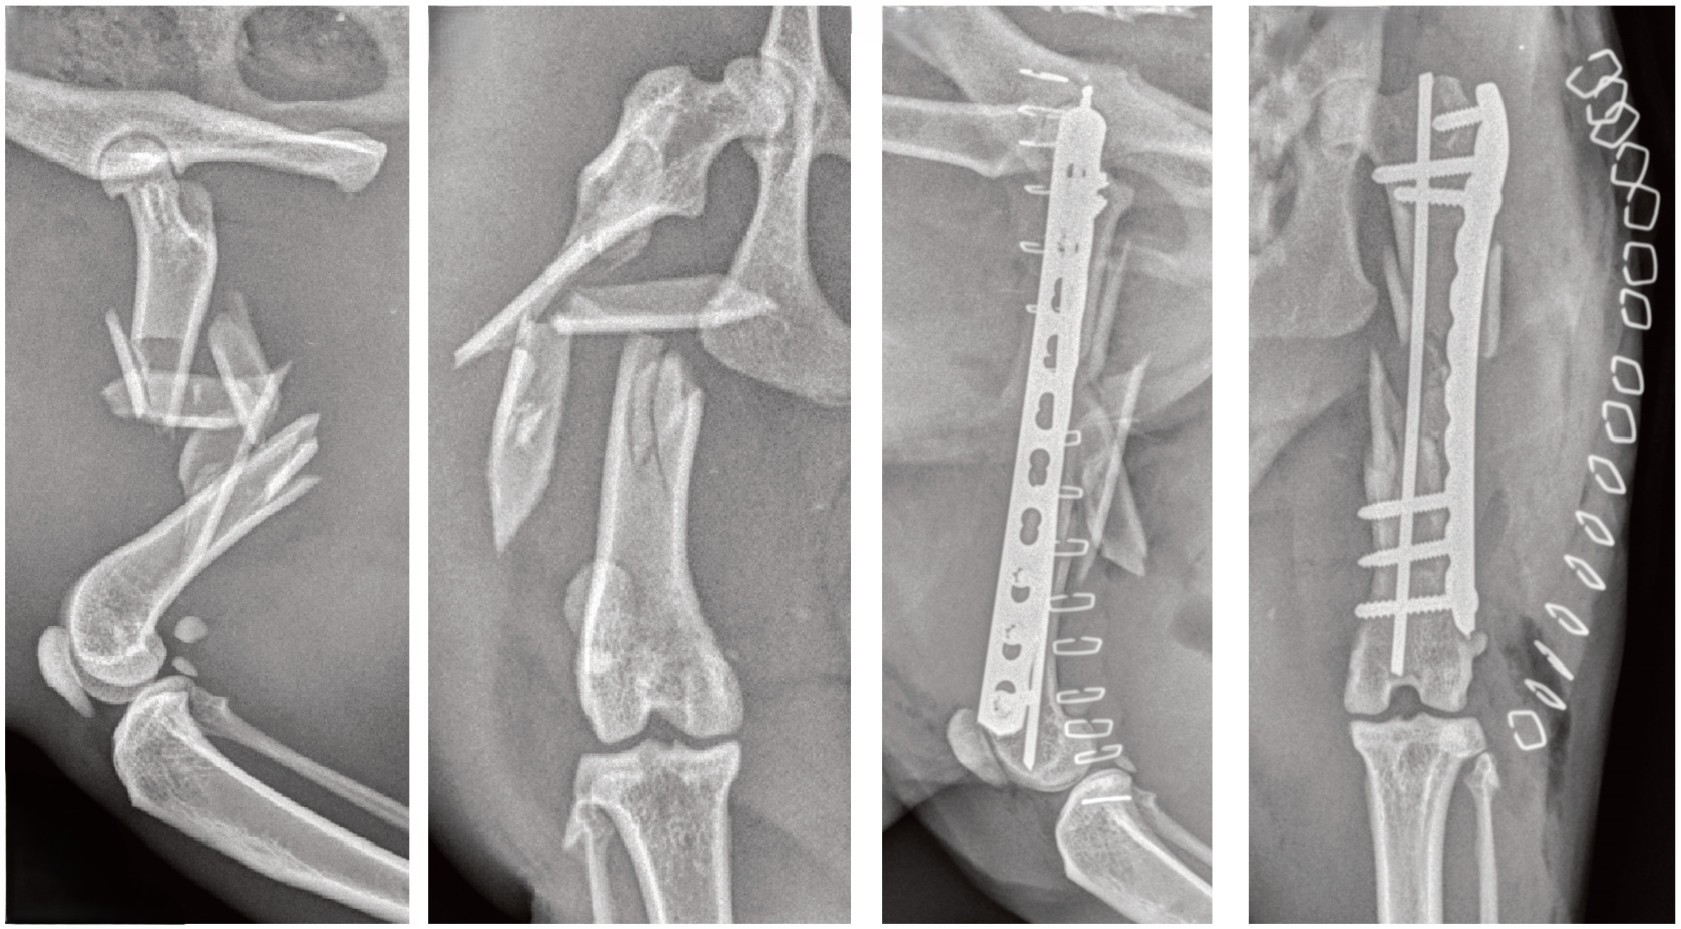

Bone Plate + Screws

Bone plates and screws are used most commonly due to their strength and versatility. The plate can be augmented with pins and wires to improve the strength of the construct or to stabilize small fragments.

Comminuted femur fracture in a cat